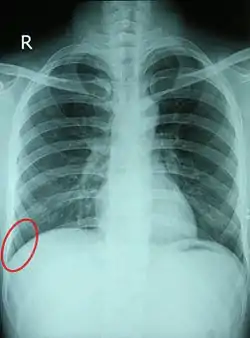

![]() Chest X-ray of a 30-year-old healthy man, with the costodiaphragmatic recess label in red ellipse | |

The costodiaphragmatic recess, also called the costophrenic recess or phrenicocostal sinus,[1] is the posterolateral fringe of the pleural space, a potential space around the lung inside the pleural cavity. It is located at the acutely angled junction ("reflection") between the costal and diaphragmatic parietal pleurae, and is interpreted two-dimensionally on plain X-rays as the costophrenic angle. It measures approximately 5 cm (2.0 in) vertically and extends from the eighth to the tenth rib along the mid-axillary line.

Each costophrenic angle can normally be seen as on chest x-ray as a sharply-pointed, downward indentation (dark) between each hemi-diaphragm (white) and the adjacent chest wall (white). A small portion of each lung normally reaches into the costophrenic angle. The normal angle usually measures thirty degrees.